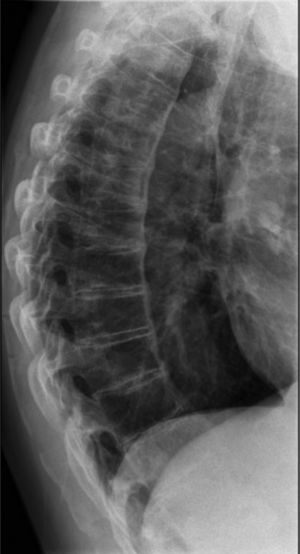

Our hospital performed X-rays of the cervical, dorsal, lumbar and pelvic spine which showed a calcification of the anterior common vertebral ligament with preservation of the disc spaces (Figs. 1 and 2).

Forestier's disease is related to abnormal bone growth.1–3 The main disease symptoms is calcification of the longitudinal ligaments of the spine, involving at least 4 contiguous vertebrae. Other criteria are the preservation of intervertebral disc spaces and the absence of inflammatory changes in intrapophysary or sacroiliac joints.4–6